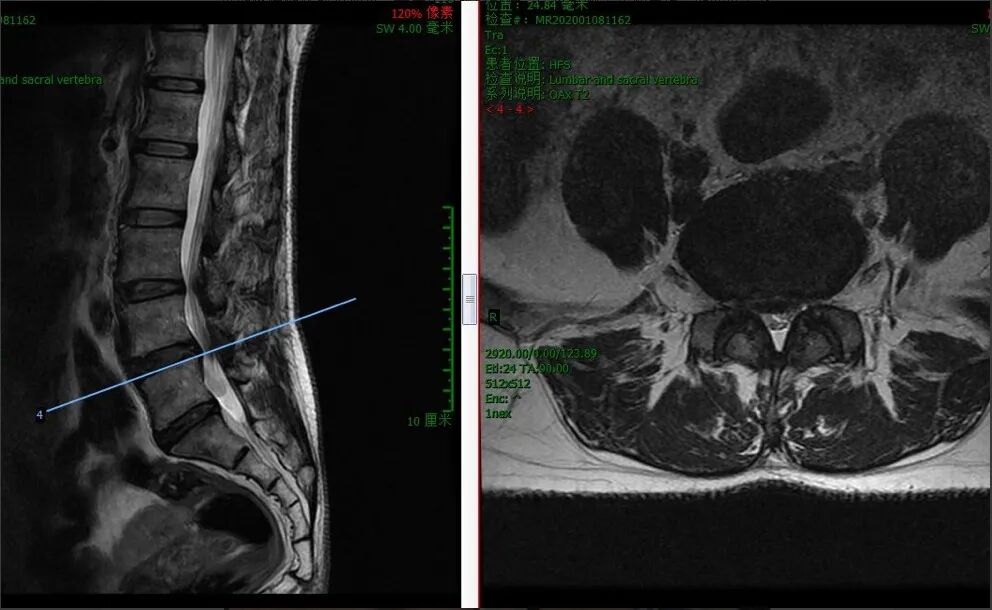

术前MR